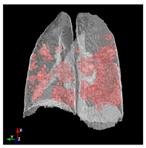

3.6. Post-Processing: 3D Projection

To generate a 3D projection from the 2D output, a post-processing step is required. This step involves aggregating the CT image slices and transforming them into a coherent 3D representation. In this process, the Mayavi [] library in Python serves as a valuable tool for facilitating the conversion of the 2D model output into a 3D representation.

The process begins by obtaining segmentation masks for each individual slice of the CT-scan. These masks provide information about the different regions within the lung. Next, the segmented slices are merged to create a unified representation. This merging process involves swapping the axes of the segmented data, ensuring that the resulting 3D projection can be visualized as a cohesive volume.

The utilization of the Mayavi library streamlines the transition of the 2D model output to a 3D representation. This library offers robust functionality for transforming and displaying the segmented data in a three-dimensional space. By employing Mayavi, the proposed approach enhances diagnostic capabilities, providing clinicians with a comprehensive 3D visualization of lung structures and infection areas.

In Table 6, a comparison of the ground truth and prediction results of each model is presented in 2D, along with the 3D projection of each model. The visual analysis of the predictions provides additional insights into the performance of each model. The visualizations demonstrate that Attention UNet captures the intricate details of the lung construction more accurately, resulting in more precise segmentation of the infected areas compared to other models.

Table 6.

Comparison of ground truth and model prediction results using UNet, LinkNet, Attention UNet, UNet 3+, and TransUNet.